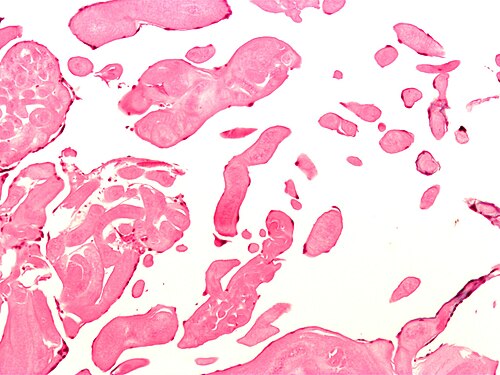

75 year old woman, dyspnea, mass on valve.

Aortic valve.

Low magnification. H&E stain.

No constitutional symptoms. Mass discovered incidentally during work-up for a pacemaker.

Looks benign. Most common heart valve tumour.